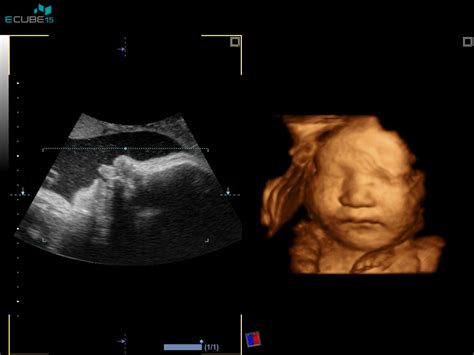

Sam ultrazvočni pregled za merjenje nuhalne svetline je neboleč in varen postopek. Najpogosteje se izvaja transabdominalno, torej preko trebušne stene nosečnice. V redkih primerih, ko je slika manj jasna, se lahko uporabi tudi transvaginalni ultrazvok. Med pregledom ultrazvočna sonda oddaja zvočne valove, ki se odbijajo od tkiv v telesu, računalnik pa te odboje pretvori v sliko. Ta sodobna tehnologija omogoča izjemen vpogled v notranjost maternice.

Med merjenjem nuhalne svetline lahko ultrazvok prikaže tudi živahno gibanje otroka. Zdravnik bo plod izmeril od temena do trtice, pregledal roke in noge, trebušno steno, hrbtenico, glavo in njene ključne dele, možgane, želodec. Poskuša se locirati srčne votline ter vizualizirati sečni mehur, ki je po 12. tednu nosečnosti običajno že viden, če ledvice delujejo pravilno. Poleg tega se preveri število žil v popkovini, oceni se položaj posteljice in količina plodovnice.